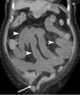

Incarcerated hernia

A hernia is the abnormal exit of tissue or an organ, such as the bowel, through the wall of the cavity in which it normally resides. Hernias come in a number of types. [Source: Wikipedia ]